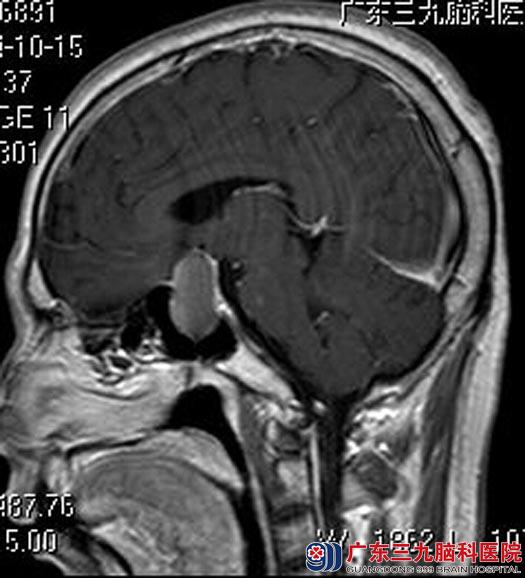

就诊广东三九脑科医院垂体瘤诊疗中心,进一步MR检查发现:鞍区一类哑铃状占位性病变,大小约1.6cm×1.8cm×3.1cm,考虑垂体瘤并卒中可能性大。

考虑到田先生的病情发展时间短、进展快,完善相关检查后,立即由鲁明主任主刀,在全麻下行经鼻蝶入路垂体瘤切除术,术中再次导航定位,显微镜下切除肿瘤组织,垂体保护完好,未见明显脑脊液漏。术后田先生的眼睛基本恢复正常。术后病理结果:垂体腺瘤伴出血。